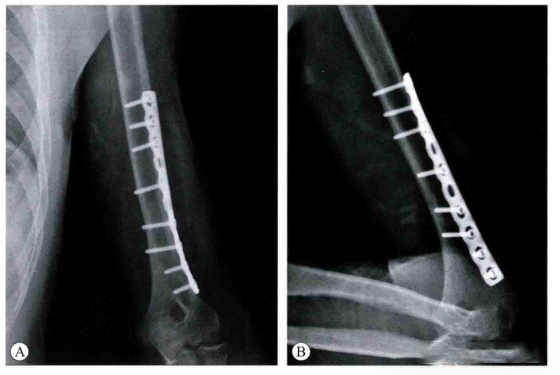

Послеоперационные рентгеноскопические снимки:

Дело 1:

Дело 2: